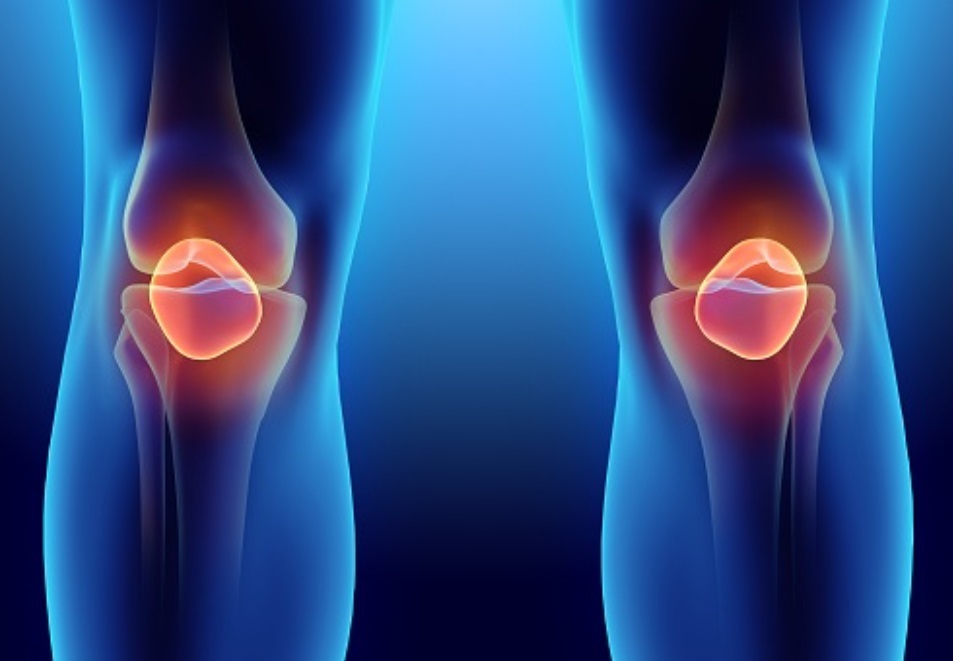

무릎통증 원인 퇴행성관절염

무릎관절염은 고나절과 연골을 보호하고 있는 연골이 점차 퇴행성 병변이 생겨서 마모되고 그로 인해 뼈와 인대가 손상이 일어나서 염증과 통증을 일으키는 퇴행성 질환을 대부분을 이야기합니다.

대부분 중년, 노년층에 나타나는 퇴행성 관절이며, 보통 노화로 인한 경우가 가장 많습니다.

하지만 오늘날에는 비만 그리고 과도한 다이어트 후유증, 과도한 운동 또는 운동 부족으로 인해서 근육이 위축되어 생기는 것이 원인이기도 합니다.

무릎관절염 자체가 점점 앞으로 활동량이 많고 무릎 사용량의 운동이 많아지기에 사람들 발생연령이 점점 낮아지는 추세이기도 합니다.